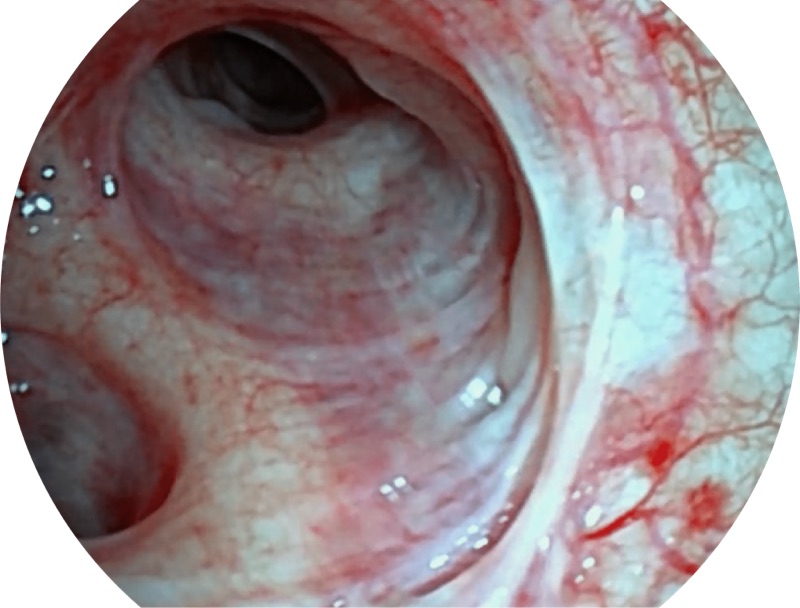

• 更细外径

EB-5H20具有4.9mm外径及2.0mm钳道提升对外围支气管检查能力